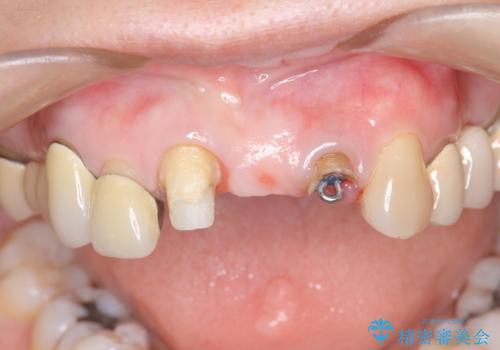

- 前歯の審美障害、見た目の改善を希望され来院されました。

歯肉縁下カリエスも認められるため、挺出を行いセラミックブリッジを審美的に新製します。

- 47万円(仮歯×3・ファイバーコア×2・ジルコニアクラウン×3 歯の挺出)費用は治療当時の料金となります